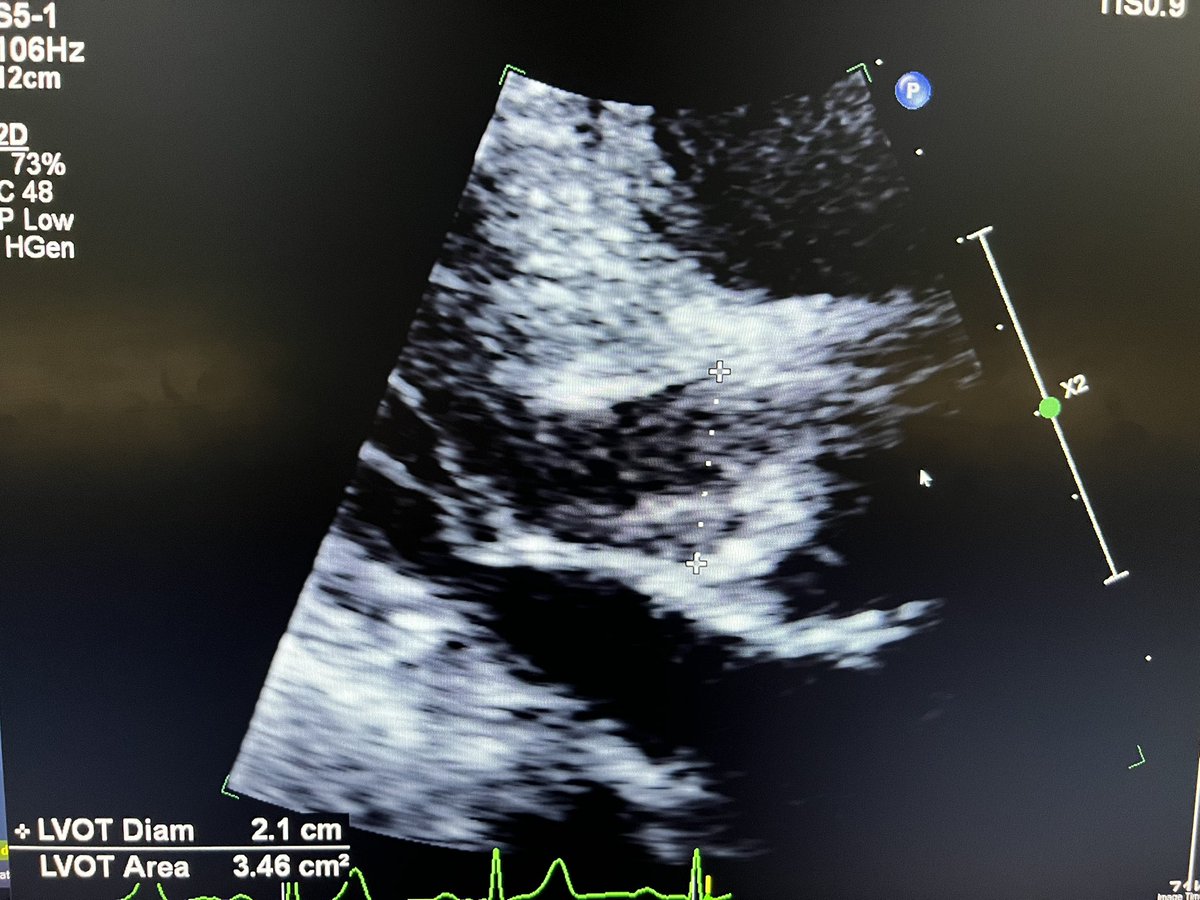

Confusing case of mod/sev AS.

Valve looks calcified but the gradients are discordant . Keen to know everyone’s thoughts @Becho2106 @echoguru @KemalogluOz @sturwohld @RobChamb87 @NMerke @echo_stepbystep @BeardedHeartDoc @kaznegishi 1/